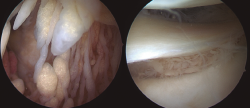

Todos los casos de hombro fueron tratados de manera artroscópica, y los hallazgos incluyeron la presencia de vellosidades características del LA (Figura 3), así como roturas en el seno del manguito rotador. Esta sinovitis proliferativa de aspecto graso se ubicaba predominantemente en la zona del intervalo rotador y en la periferia de la glena e inserción del tendón de la porción larga del bíceps.

Figura 3. Imágenes artroscópicas de las vellosidades del LA en el hombro, así como los cambios artrósicos en la articulación glenohumeral.

Figura 5. Imágenes de la toma de biopsia del LA durante la artroscopia de hombro, ubicada en la zona de la periferia del anclaje glenoideo de labrum y porción larga del bíceps, en el que cabe destacar una banda fibrosa a modo de envoltura.